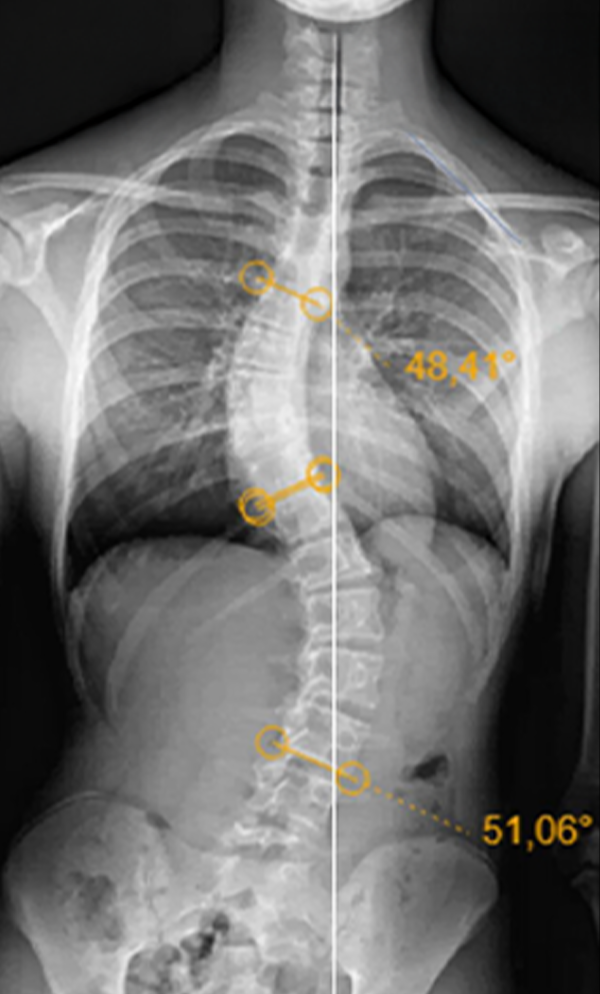

Gallery : Before - After